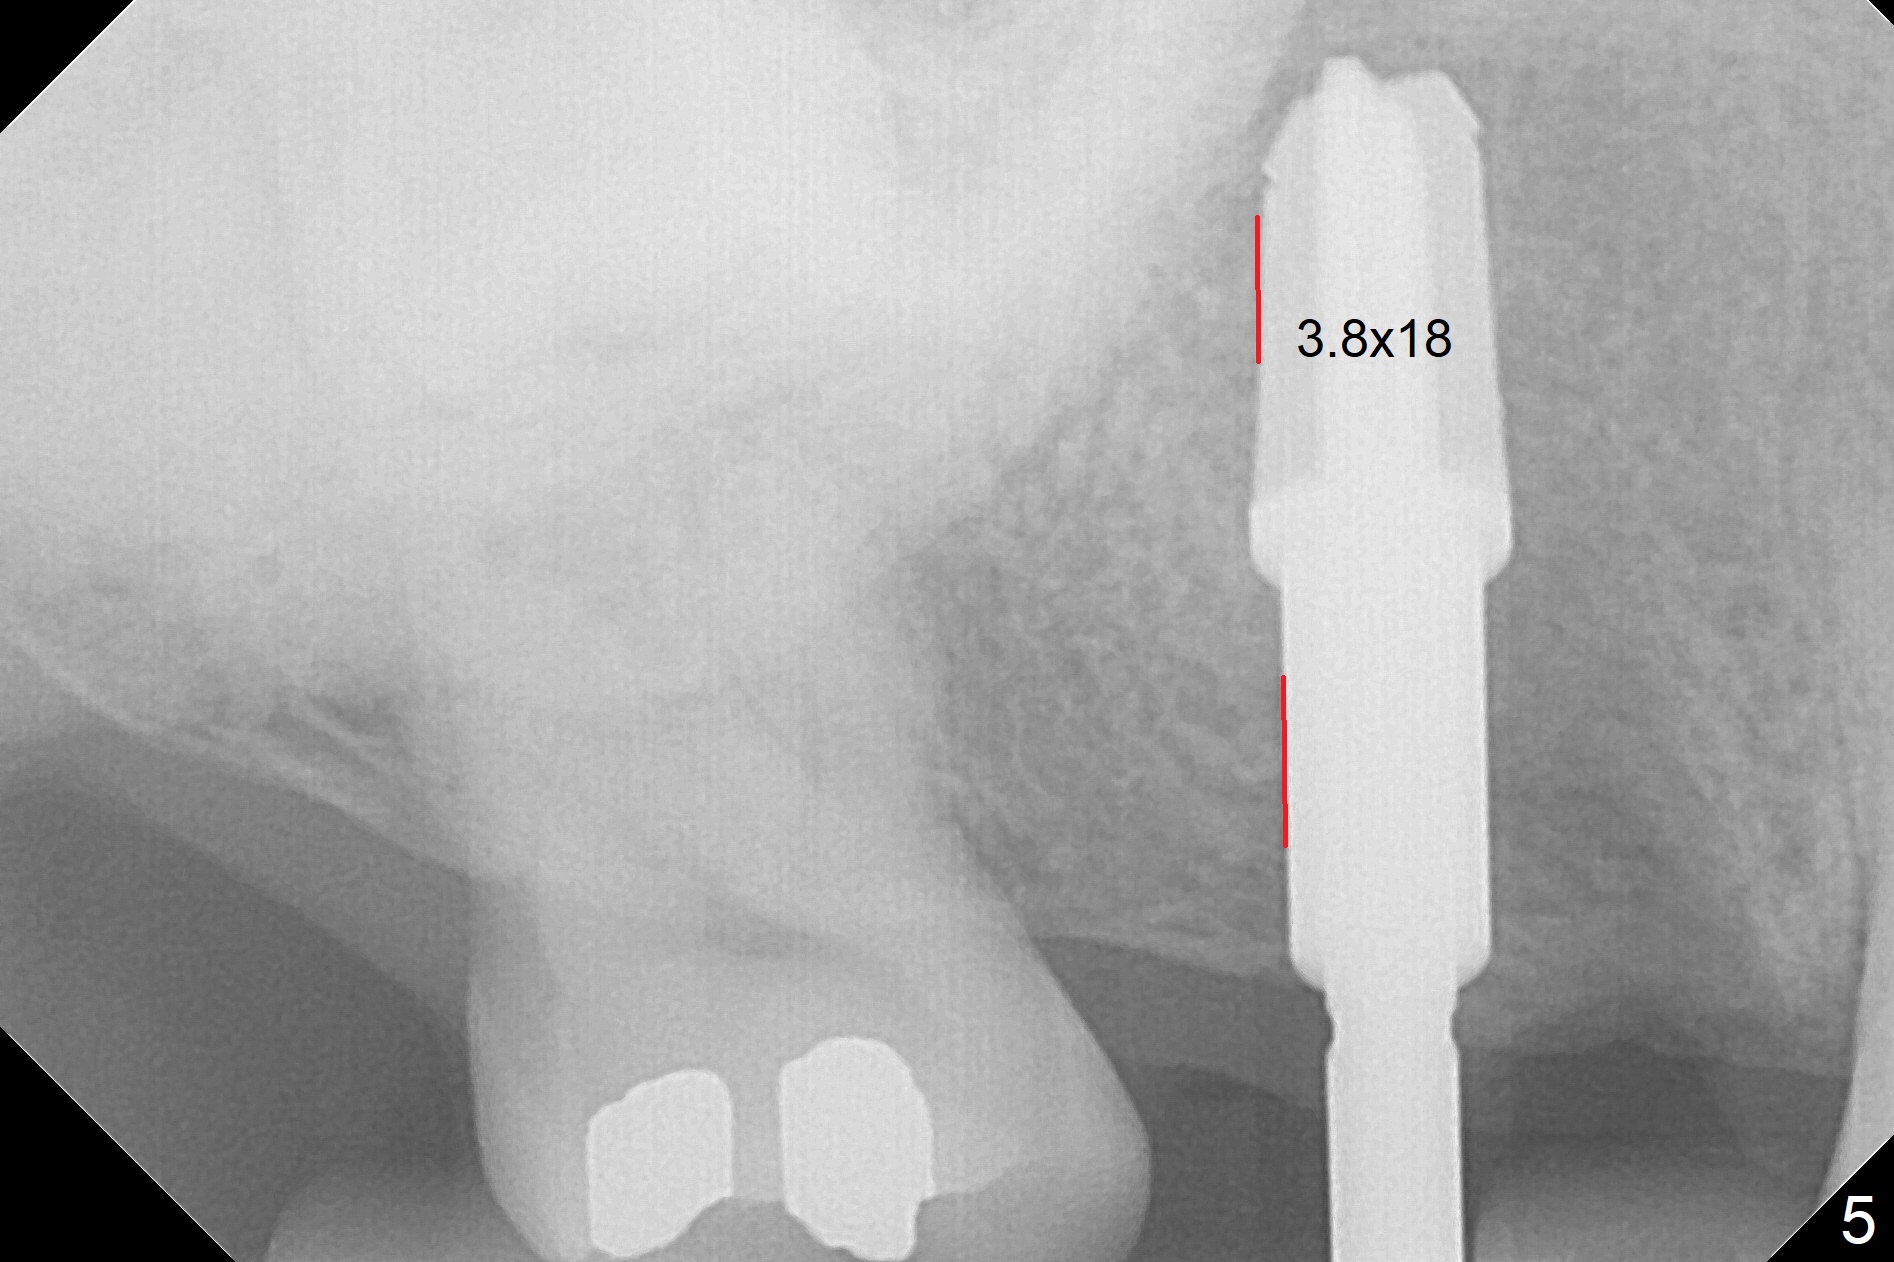

The palatal cusp of the affected 2nd premolar is apparently rotated distal (Fig.1). It is more obvious for the socket (Fig.2): the palatal (P) portion of the socket is more distal than the buccal (B) one. When the gauze is removed (Fig.3), Lindamann bur is used to remove the disto(D)palatal bone of the socket (data not shown), followed by starter drill in the DP wall obliquely (Fig.3'). Once the drill enters the bone for 1-2 mm, the bur is straightened and pushed slightly distal (Fig.3''). Fig.4 shows a parallel pin distal (overcorrect) to the original socket (Fig.4 red dashed line). Sequential osteotomy is conducted until 3.8x13 mm drill for 18 mm (Fig.5): note the 2 steps of the osteotomy (red lines). Since the apical portion of the osteotomy is larger than the drill, a larger implant than expected (5x16 mm) is placed. The implant ends up in the middle of the edentulous area (due to the stepped osteotomy; Fig.6-9; >60 Ncm). Vera allograft is placed (Fig.7-9 *) prior to and after placement of a 6.5x4(3) mm abutment (Fig.8-10). The remaining socket opening is sealed with a piece of Collagen plug (Fig.10 *). The socket is then closed by an immediate provisional (Fig.11 P). The abutment is retightened 2 months postop (Fig.12,13). The crown is cemented 4.5 months postop. Panoramic X-ray and CT are taken nearly 7 months post cementation (Fig.14,15) when the patient is ready for #30 implant guide preparation.